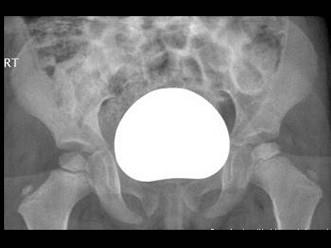

问题 女,4岁,左腿跛行2个月。请结合图片,选出最可能的诊断 ( )

选项 A、髋关节结核 B、股骨头骨骺缺血坏死 C、软骨肉瘤 D、骨肉瘤 E、骨囊肿

答案 B